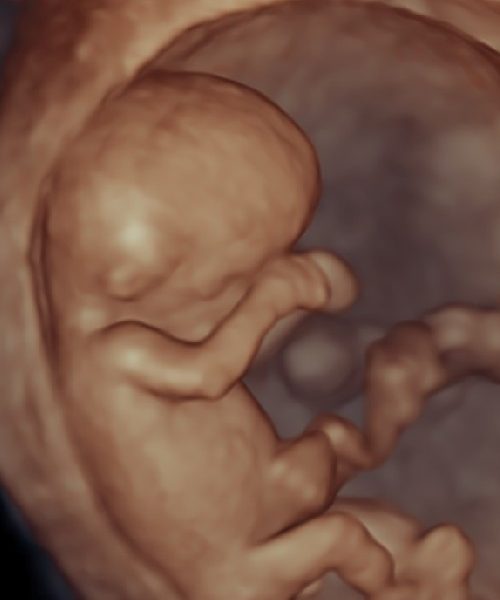

El elegir un centro de especialidad certificado garantiza una evaluación profesional del paciente, así como disponer de informes y resultados confiables. Contamos con la preparación académica en la evaluación mediante la ecografía y medicina fetal, que avala nuestro compromiso con la salud y bienestar de nuestros pacientes. Conozca más.

SERVICIOS DE ESPECIALIDAD

GINECOLOGÍA, PLANIFICACIÓN, EMBARAZO DE ALTO RIESGO, ECOGRAFÍA Y MEDICINA FETAL